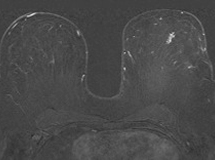

Vor der MRT-gestützten Biopsie wird wie bei der MRT-Untersuchung ein venöser Zugang in die Ellenbeuge gelegt. Anschließend wird die Patientin in Bauchlage gelagert und die Brust wird in der MRT-Brustspule platziert. Nach intravenöser Verabreichung eines Kontrastmittels wird der zu untersuchende Befund in der Brust genau geortet und die Biopsie geplant.